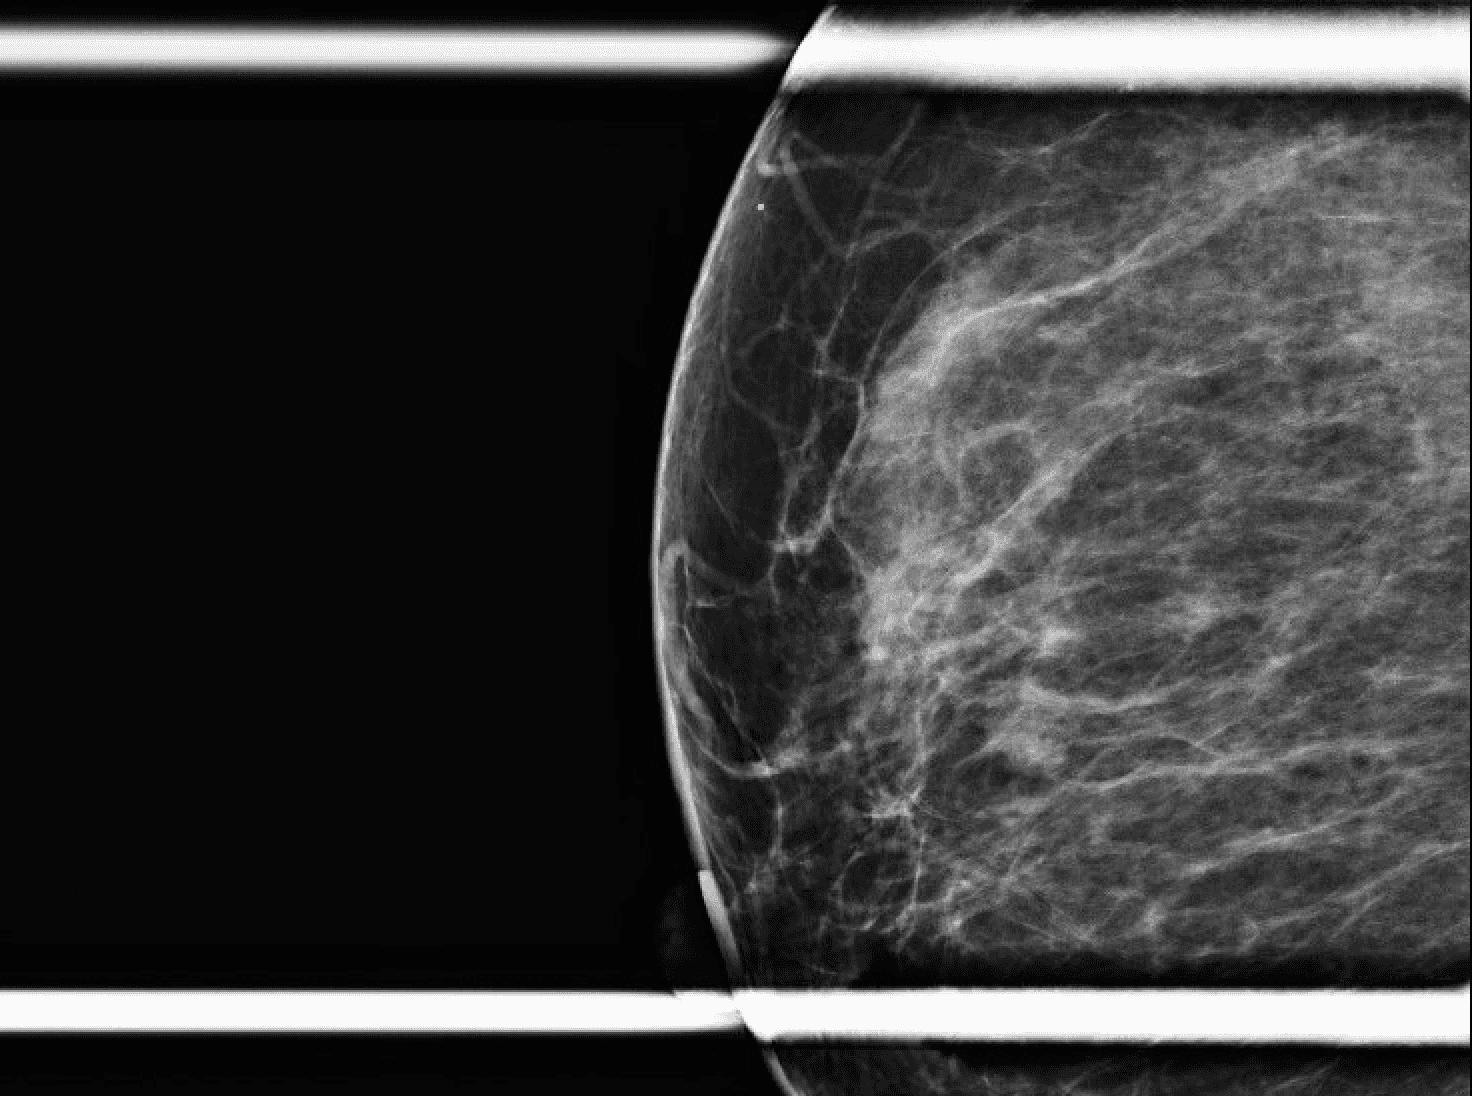

Patient is a 46-year-old premenopausal female with no other contributing past medical or surgical history who presented initially to the breast surgery clinic after her annual screening mammogram discovered a nonpalpable right breast mass measuring 0.6 x 0.8 x 0.7 cm at 11 o’clock (oc), 1 cm from the nipple (FTN) (Figure 1). She had three previous screening mammograms without any notable findings. The screening mammogram was declared inconclusive (BI-RADS 0), and a breast ultrasound was completed with similar findings. Further discussion with the patient revealed that there had been some bloody discharge seen in the right side of her bra over the last few months, but no other concerns or symptoms. Given the inconclusive imaging findings, it was decided to perform a diagnostic mammogram for a more specific assessment (Figures 2a and 2b) following an ultrasound-guided core-needle biopsy and localizing clip placement for a tissue diagnosis (Figure 3). Pathology revealed an intraductal papilloma with ductal hyperplasia and apocrine metaplasia without atypia. Given her continued bloody nipple discharge, there was concern for possible underlying premalignant cells (discussed more later); thus, it was recommended that the patient undergo partial mastectomy. The mass remained nonpalpable; therefore, a Savi Scout would be placed just before operative intervention to help localize the area of concern.

Figure 1. Initial screening mammogram (R mediolateral orientation, followed by craniocaudal). Revealed the concerning area of question measured to be approximately 0.6 x 0.8 x 0.7 cm in size, located at 11 oc and 1 cm FTN.